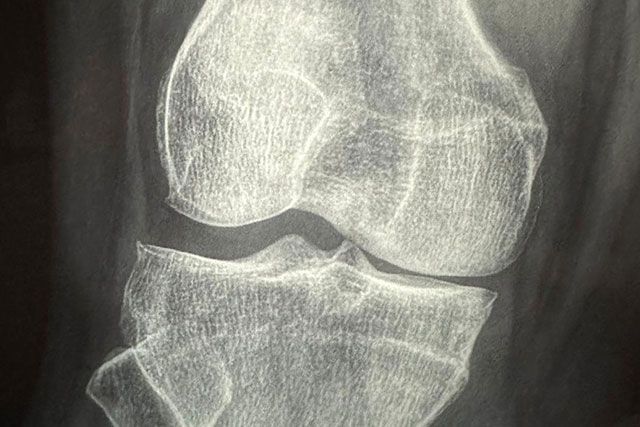

- Lesiones de ligamentos cruzados y meniscos

- Fracturas por estrés o impacto

Se realiza un abordaje integral que incluye diagnóstico clínico y por imagen (rayos X, ultrasonido, resonancia), plan terapéutico individualizado y asesoría para el retorno seguro al deporte.